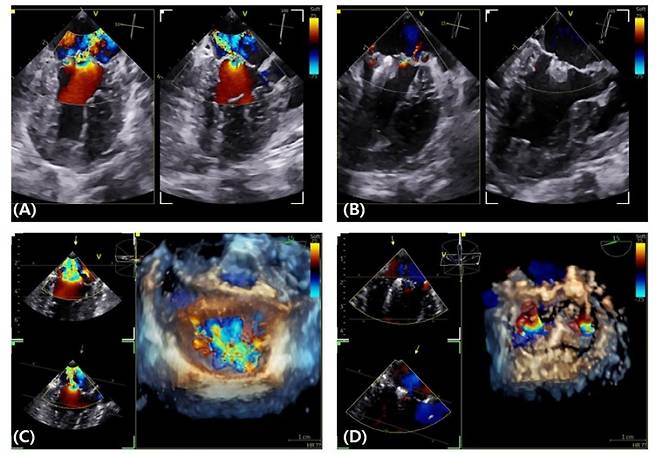

내과 수의사인 이정민 박사는 "약물치료와 수술 중 어느 쪽이 환자에게 더 적합한지를 평가하는 것이 핵심"이라며 "경식도 초음파를 활용한 3D 심장 구조 분석이 치료 판단에 결정적인 도움을 준다"고 강조했다.